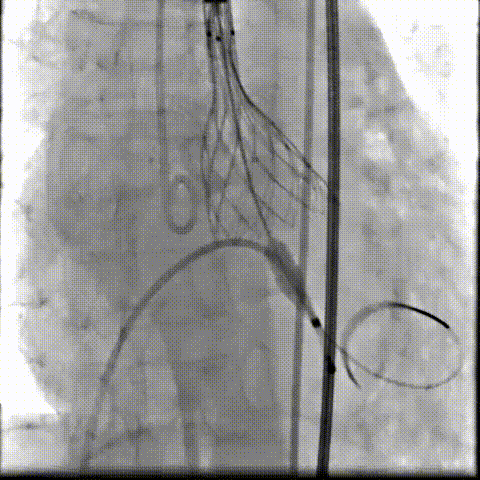

瓣膜工作位释放“烟囱支架”;

瓣膜(AV23)完全释放后,“烟囱支架”后扩

最终造影,“烟囱支架”显影清晰,瓣膜形态及LCA灌注良好

超声影像

TEE影像,烟囱支架显影清晰,支架内血流通畅